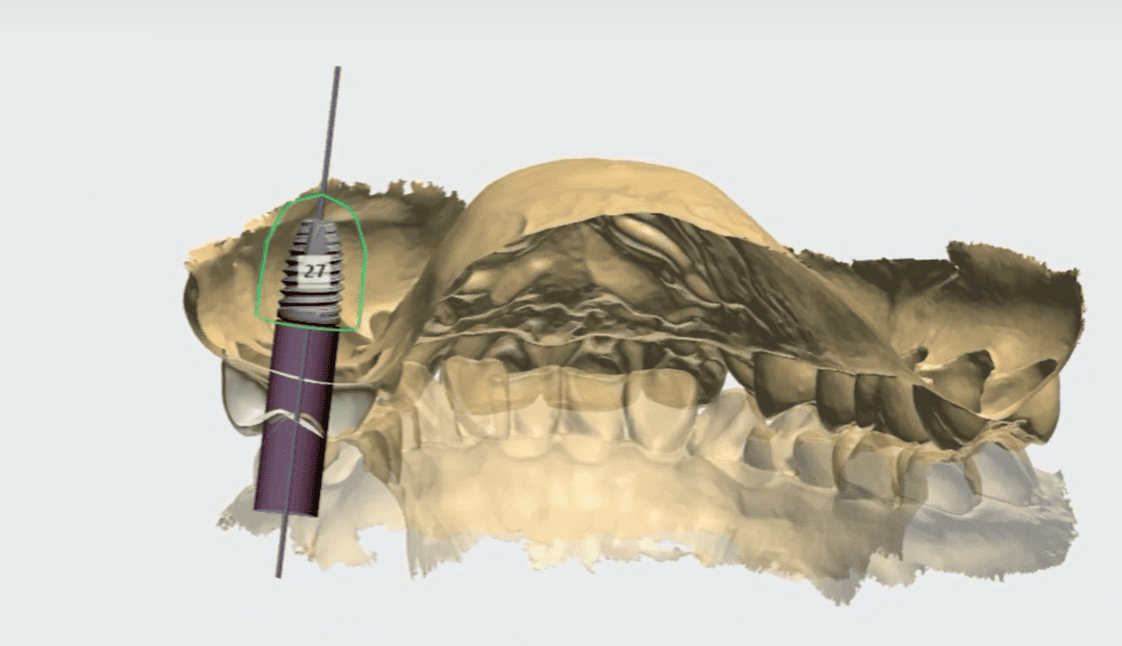

電腦模擬植牙位置

在手術前先透過軟體模擬植體角度與位置,降低手術誤差。

這些數位技術能讓植牙規劃更精準,也能幫助醫師提前預判風險。